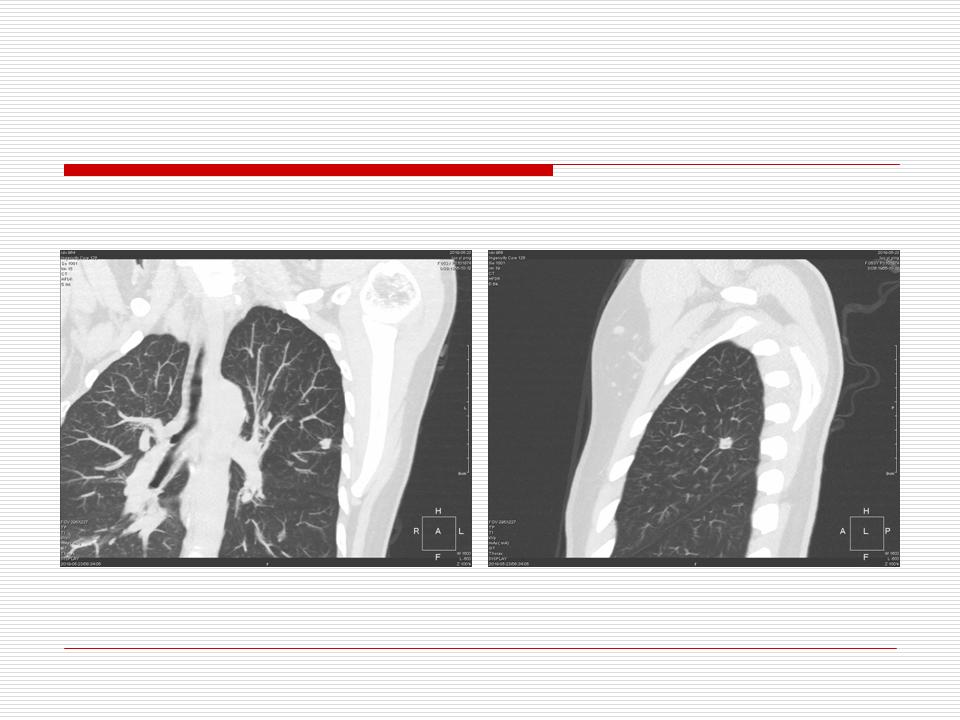

肺部阴影永恒且最重需要鉴别的是:到底是炎症还是肿瘤?但临床的病例中的影像表现难以界定或有些肿瘤特征,同时又有些炎症特点是非常常见的情况。作为临床医生我们怎么去总结分析,并找到之所以是炎症或之所以是肿瘤的细微差别或特点非常重要,也非常有用。2019.12.7浙江省2019年胸心外科学学术年会在宁波召开时,我的临床病例分析与经验总结<那些像肺癌的炎症与像炎症的肺癌>获得在大会交流的机会,以下为该PPT的内容,与你分享,希望对同道有益,有借鉴与启迪。若有探讨与进一不完善的建议,欢迎文末留言讨论: